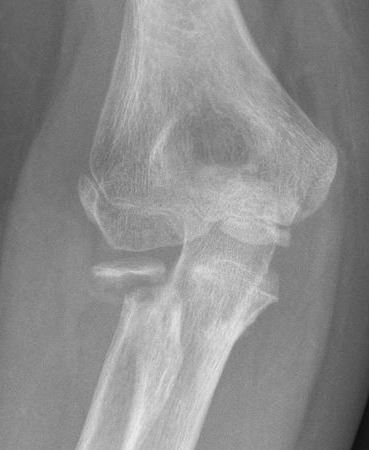

Radial neck fracture and olecranon fracture